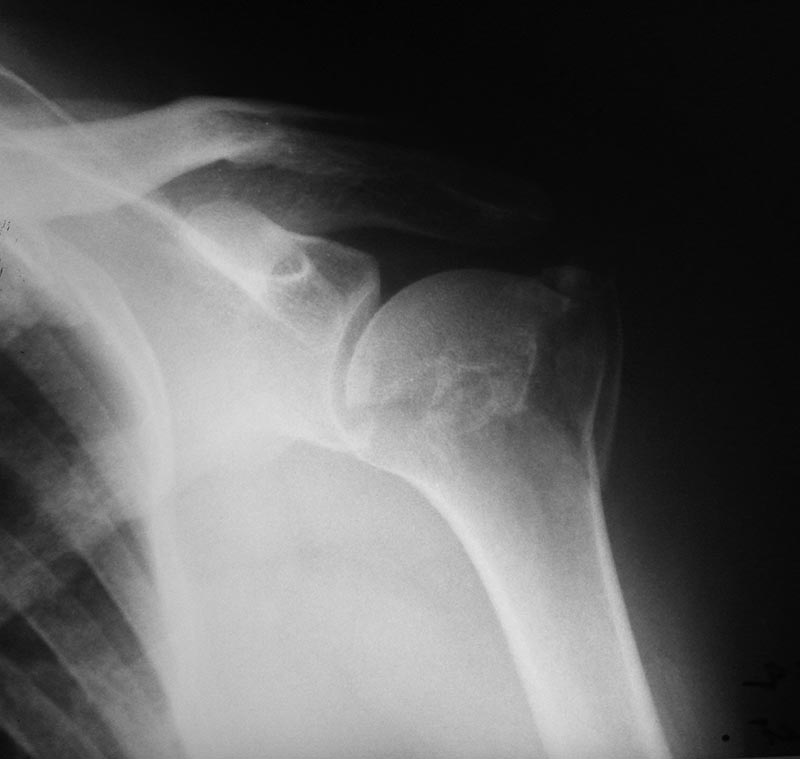

Перелом шейки плеча

Пациентка 60 лет. Работает художником.

Хотелось бы услышать мнение: оперативное или консервативное лечение.

Вколоченный вальгусный 4-фрагментный перелом. Вот свежая статья бразильских коллег по теме.

Роман,сделайте КТ,получите больше объема инф. при такой высокоэнегетической травме есть риск асептического некроза головки,удачи!